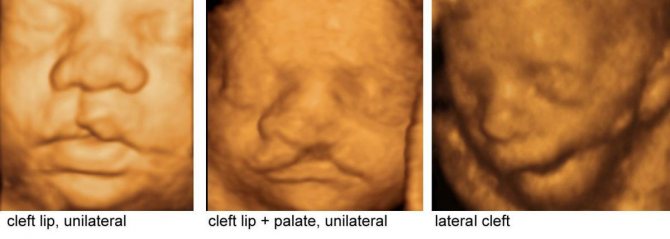

Типы дефектов

Две большие группы анатомических дефектов классифицируются, исходя из различных признаков.

Классификация хейлосхизиса:

• По стороне поражения

Одностороннее расщепление (чаще всего слева);

• Двустороннее расщепление, симметричное и несимметричное.

• Классификация расщепления неба (волчьей пасти)

Принципы классификации срединного расщепления верхнего неба немного иные.